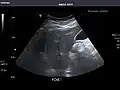

Pancreas -

Pancreas: Visualized portions unremarkable.